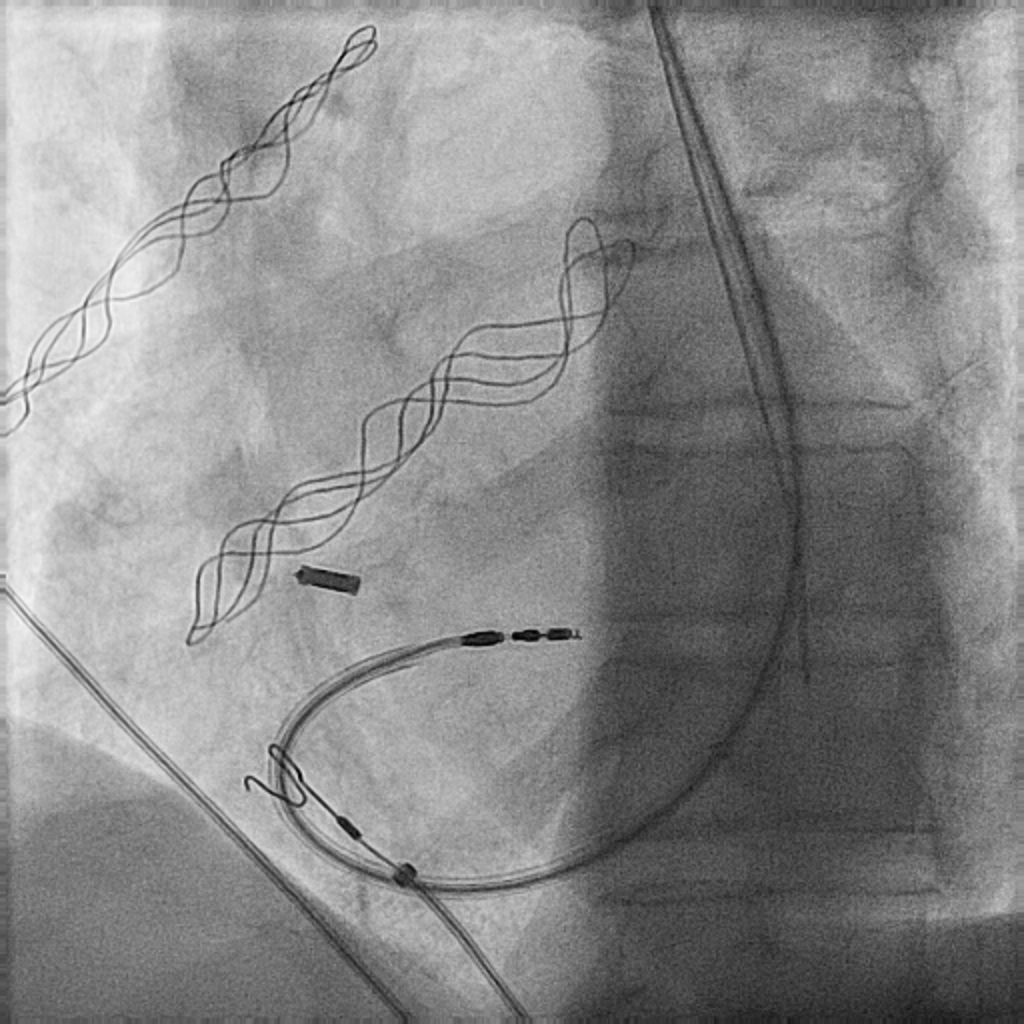

80 y/o M with NICM LVEF 45% with VT storm & ICD shocks. Earliest activation noted intramurally in AIV septal perforator vein via Vision wire. Not early in cusps, endo LV summit or RVOT. Successful ablation with long lesions in LV endocardium opposite the wire.